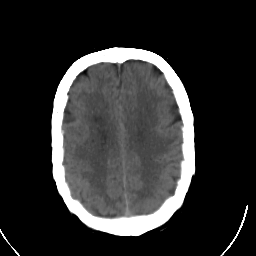

Stroke CT #3 -- Slice #18

[Home][Help][Clinical] Slice 18